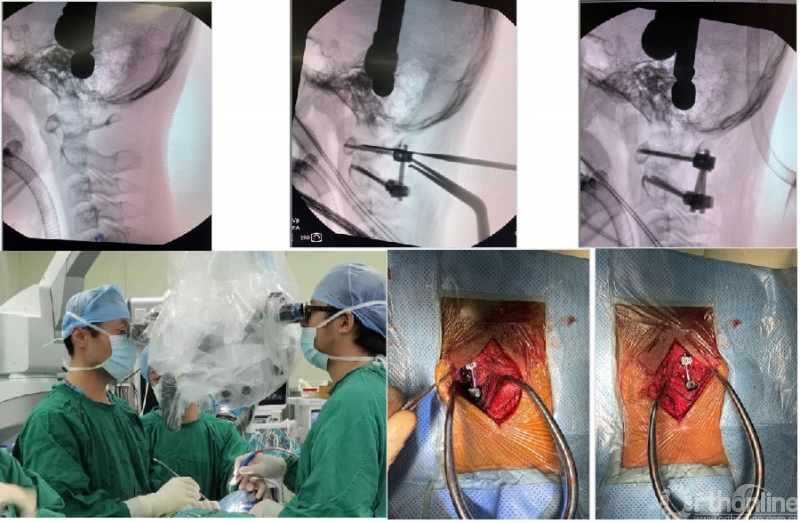

图2:经口松解术:第一步松解前方的韧带和肌肉结构;第二步松解寰枢椎侧块关节的粘连和齿突侧方的翼状韧带;第三步松解齿突尖韧带,向下轻轻牵拉齿突、齿突尖可以被拉出。说明松解完成、达到复位。

常规的寰枢椎后路融合术需行颈后部肌肉的剥离。颈后部伸肌及枕下小肌群全部需要剥离,还需要髂骨取骨。术后颈后部轴性疼痛和取骨区的疼痛困扰着患者及术者。近年来,北医三院颅椎组开展了显微镜下经双侧肌肉间隙的寰枢椎融合术。保留了颈后伸肌张力带、同时从C2椎板和棘突根部取少许骨质,植入侧块间隙。

北医三院颅椎组致力于寰枢关节融合术的微创化治疗。该技术的创新点包括:

1. 显微镜辅助下操作,手术切口小;

2. 术中神经保护严格,术中失血少;

3. 保留枕下肌群的伸肌止点,对肌肉功能影响少;

4. 侧块间隙少量植骨即可保证可靠骨性融合、避免了取髂骨的并发症。